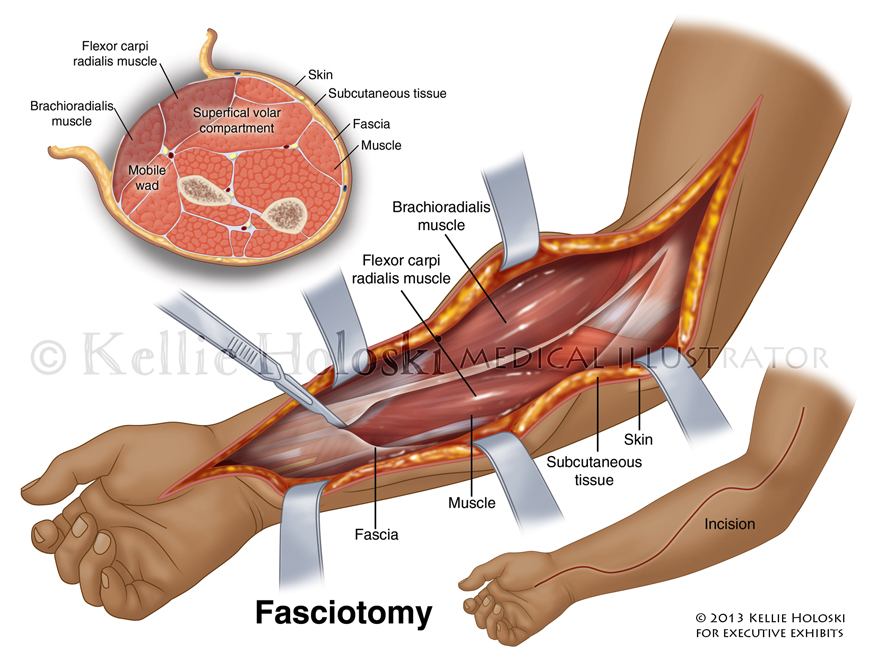

Fasciotomy,

Adobe Photoshop

Courtroom exhibit for Executive Exhibits;

©Kellie Holoski -